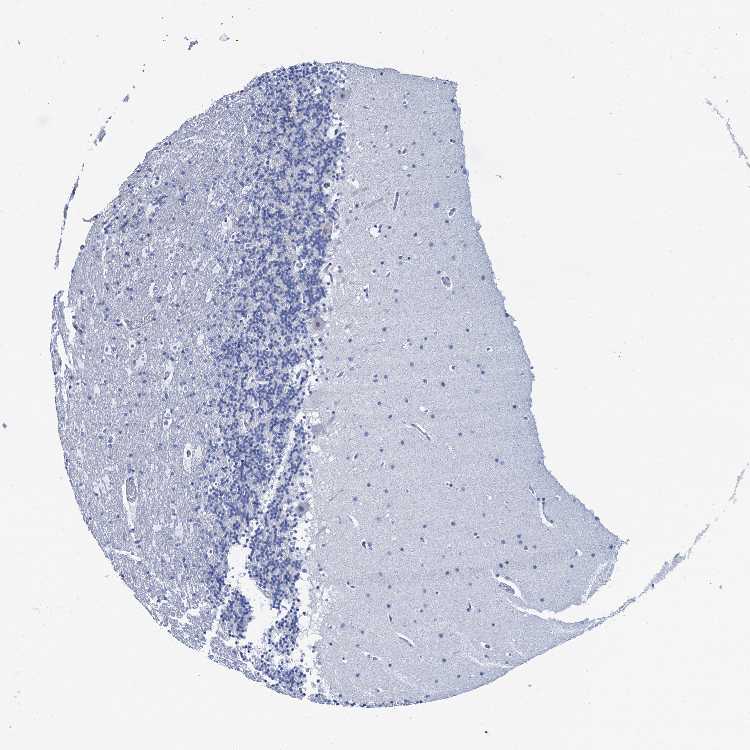

BRAIN CEREBELLUM Show tissue menu

CEREBELLUM - Expression summary

CEREBELLUM - Antibody stainingi

Antibody staining in the annotated cell types in the current human tissue is reported as not detected, low, medium, or high, based on conventional immunohistochemistry profiling in selected tissues. This score is based on the combination of the staining intensity and fraction of stained cells.

Each image is clickable and will lead to virtual microscopy that enables deeper exploration of all samples and also displays staining intensity scores, fraction scores and subcellular localization as well as patient and tissue information for each sample.

Antibody HPA040703Antibody HPA047801

Purkinje cells Not detectedNot detected

Cells in granular layer Not detectedNot detected

Cells in molecular layer Not detectedNot detected